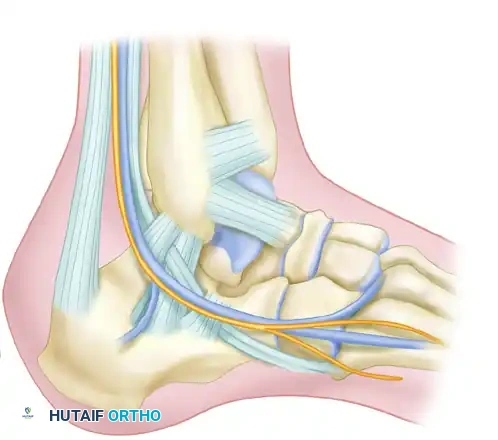

SURGICAL ANATOMY AND BIOMECHANICS

Understanding the vascular anatomy of the lateral hindfoot is paramount. The lateral calcaneal artery, a terminal branch of the peroneal artery, supplies the lateral skin flap. The extensile lateral approach is designed as a full-thickness, subperiosteal flap to protect this delicate angiosome.

The sural nerve courses along the lateral aspect of the hindfoot and is at risk during both the proximal and distal extensions of the incision. The peroneal tendons (brevis and longus) lie within the surgical field and must be elevated en bloc within the soft tissue flap to prevent iatrogenic injury or postoperative subluxation.